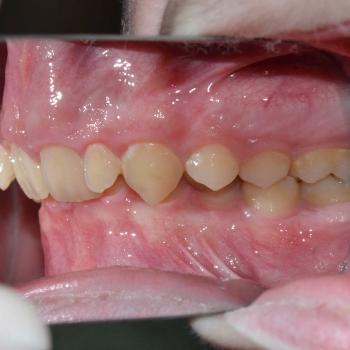

Balázs és édesanyja konzultáció céljából keresett fel, hogy egyértelműen kiderüljön számukra szükséges-e a fogszabályozó kezelés vagy sem. Már rögtön az első vizsgálat alkalmával fény derült több olyan problémára is, melyek fogszabályozást igényelnek. Ilyen volt például a súlyos mélyharapás, a hátrafelé dőlő felső metszők, illetve az Angle II. osztályú harapási eltérés is. A mintavétel, a röntgenek és a fotók kiértékelése után további problémaként merült fel a felső fogív szűkülete és a kismetszők méretaránytalansága, azaz a túlzott keskenységük.

A kezelést Quadhelix fogszabályozóval kezdtük el a felső fogív tágítása érdekében. Ezután került felragasztásra az alsó és felső fogívre a Balázs és szülei által kiválasztott fém önligírozó fogszabályozó. Ezen túlmenően Bite turbo harapásemelő segített a mélyharapás, intermaxillaris gumihúzás pedig az Angle II. osztályú harapási eltérés korrigálásában. A fogak méretaránytalansága miatt a kezelés végén a kismetszőket tömőanyaggal építettük fel, hogy a tökéletes harapáshoz résmentes fogazat társuljon. A fogak felépítéséhez az adott fogakat nem kell megfúrni, a tömőanyag kizárólag ragasztásos módszerrel rögzül, így nem károsodik a fogzománc.